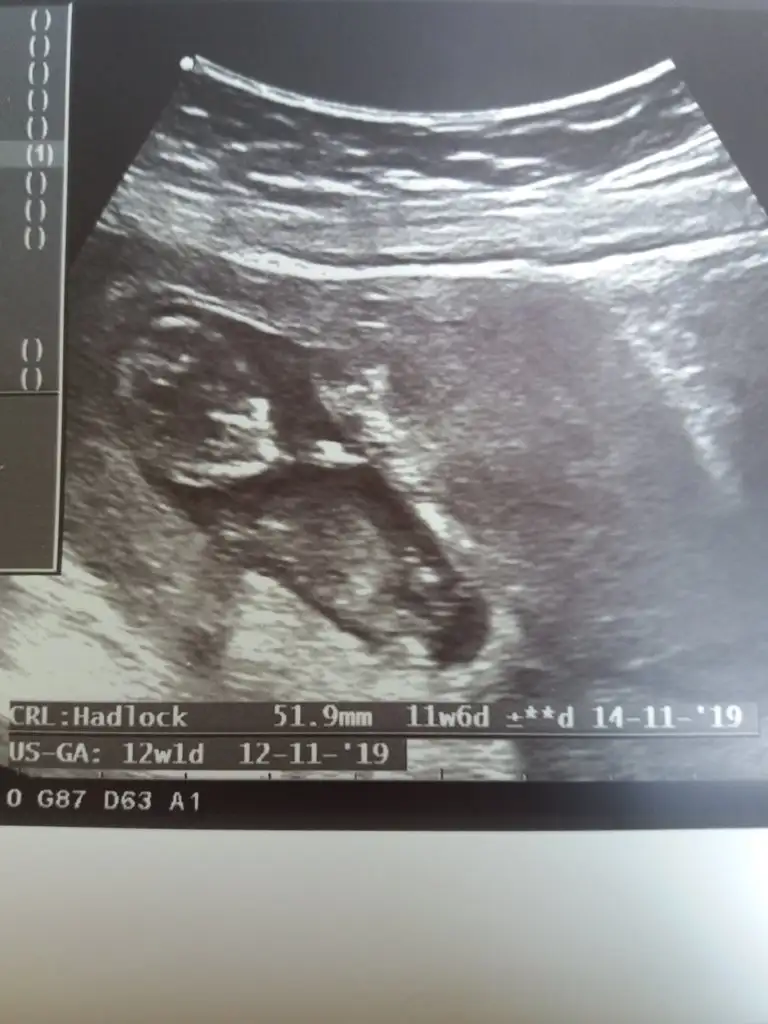

inşallah cnm sağlıkla kucağınıza alalımGünaydın kızlar, bugün 12.30da randevum var. 1 ay geçti aradan heyecan bastı. Sağlıklıdır inş herşey yolundadır. Dua edin bana da güzel haberlerle geleyim inş

hadi güzel haberlerini bekliyoruzzzAy kızlar sıramı bekliyorum kontrol icin ama heyecandan ölcem resmen